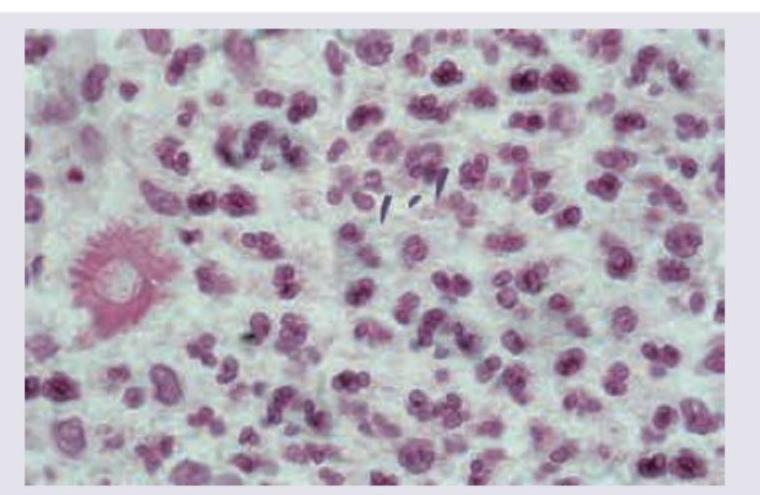

A carpenter presents with a nodule on dorsum of hand which ulcerates after few days and has not healed for last 2 months. Biopsy of lesion was performed and shown below. Diagnosis is:

Explanation: ***Sporotrichosis*** - The image shows **cigar-shaped yeast cells** (arrow), characteristic of *Sporothrix schenckii*, the causative agent of sporotrichosis. The presence of an **asteroid body** (asterisk) formed by eosinophilic material radiating from the yeast cell is also classic for sporotrichosis in tissue. - The history of a **carpenter** presenting with a nodule that ulcerates after trauma (e.g., from wood splinters) and doesn't heal is highly suggestive of **sporotrichosis**, often referred to as "rose gardener's disease" due to occupational exposure. *Chromomycosis* - Characterized by the presence of **sclerotic bodies** (also known as Medlar bodies or fumagoid bodies) which are darkly pigmented, thick-walled, round cells that divide by septation. - The clinical presentation is typically slow-growing, **verrucous plaques** or nodules, predominantly on the lower extremities, which are distinct from the ulcerating nodule seen here. *Lobomycosis* - Caused by *Lacazia loboi*, it presents with **chains of yeast cells** that are spherical or ovoid, thick-walled, and interconnected by short tubes. - Clinically, it typically manifests as **keloid-like lesions** or chronic nodular plaques, primarily in tropical and subtropical regions, and does not commonly ulcerate in the initial presentation like the case described. *Cutaneous histoplasmosis* - Caused by *Histoplasma capsulatum*, which appears as **small, oval yeast cells** (2-4 µm) within macrophages in tissue sections. - While it can manifest cutaneously, especially in immunocompromised individuals, the yeast cells are much smaller and do not have the distinct cigar-shape or form asteroid bodies seen in the image.